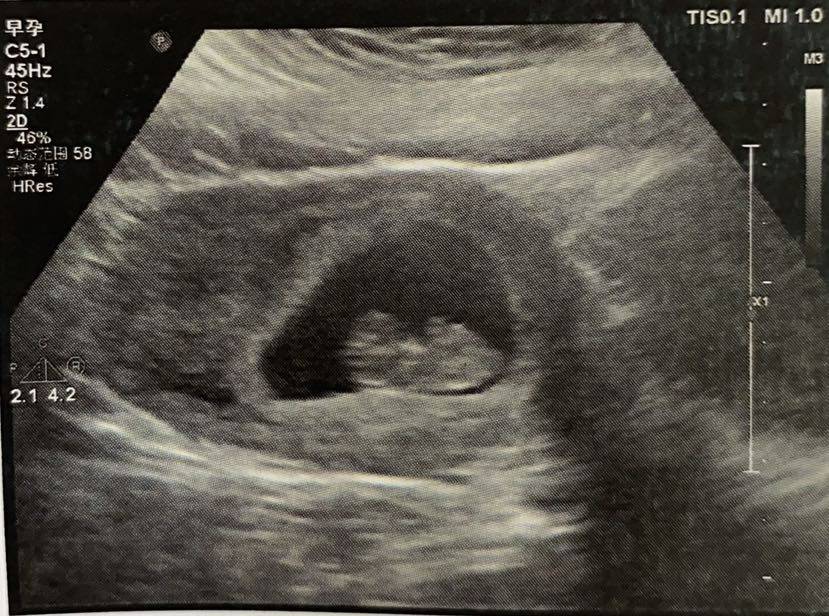

再做个阴超(简直羞耻➕痛苦)

结论:偏小一周!